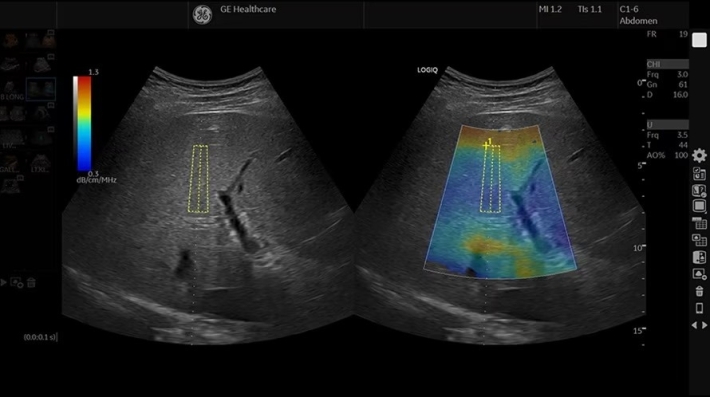

• UGAP — опция измерения затухания звуковой волны в режиме реального времени, оценка стеатоза печени в В-режиме;

• HEPATIC Assistant — программа для оценки диффузных изменений в печени с количественным определением;